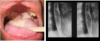

Your HIV positive patient presents with the attached physical findings.

What is this condition?

What organism is responsible for this?

This is an example of mucocutaneous candidiasis presenting as oropharyngeal/esophageal candidiasis. >90% of these will be caused by C. albicans.